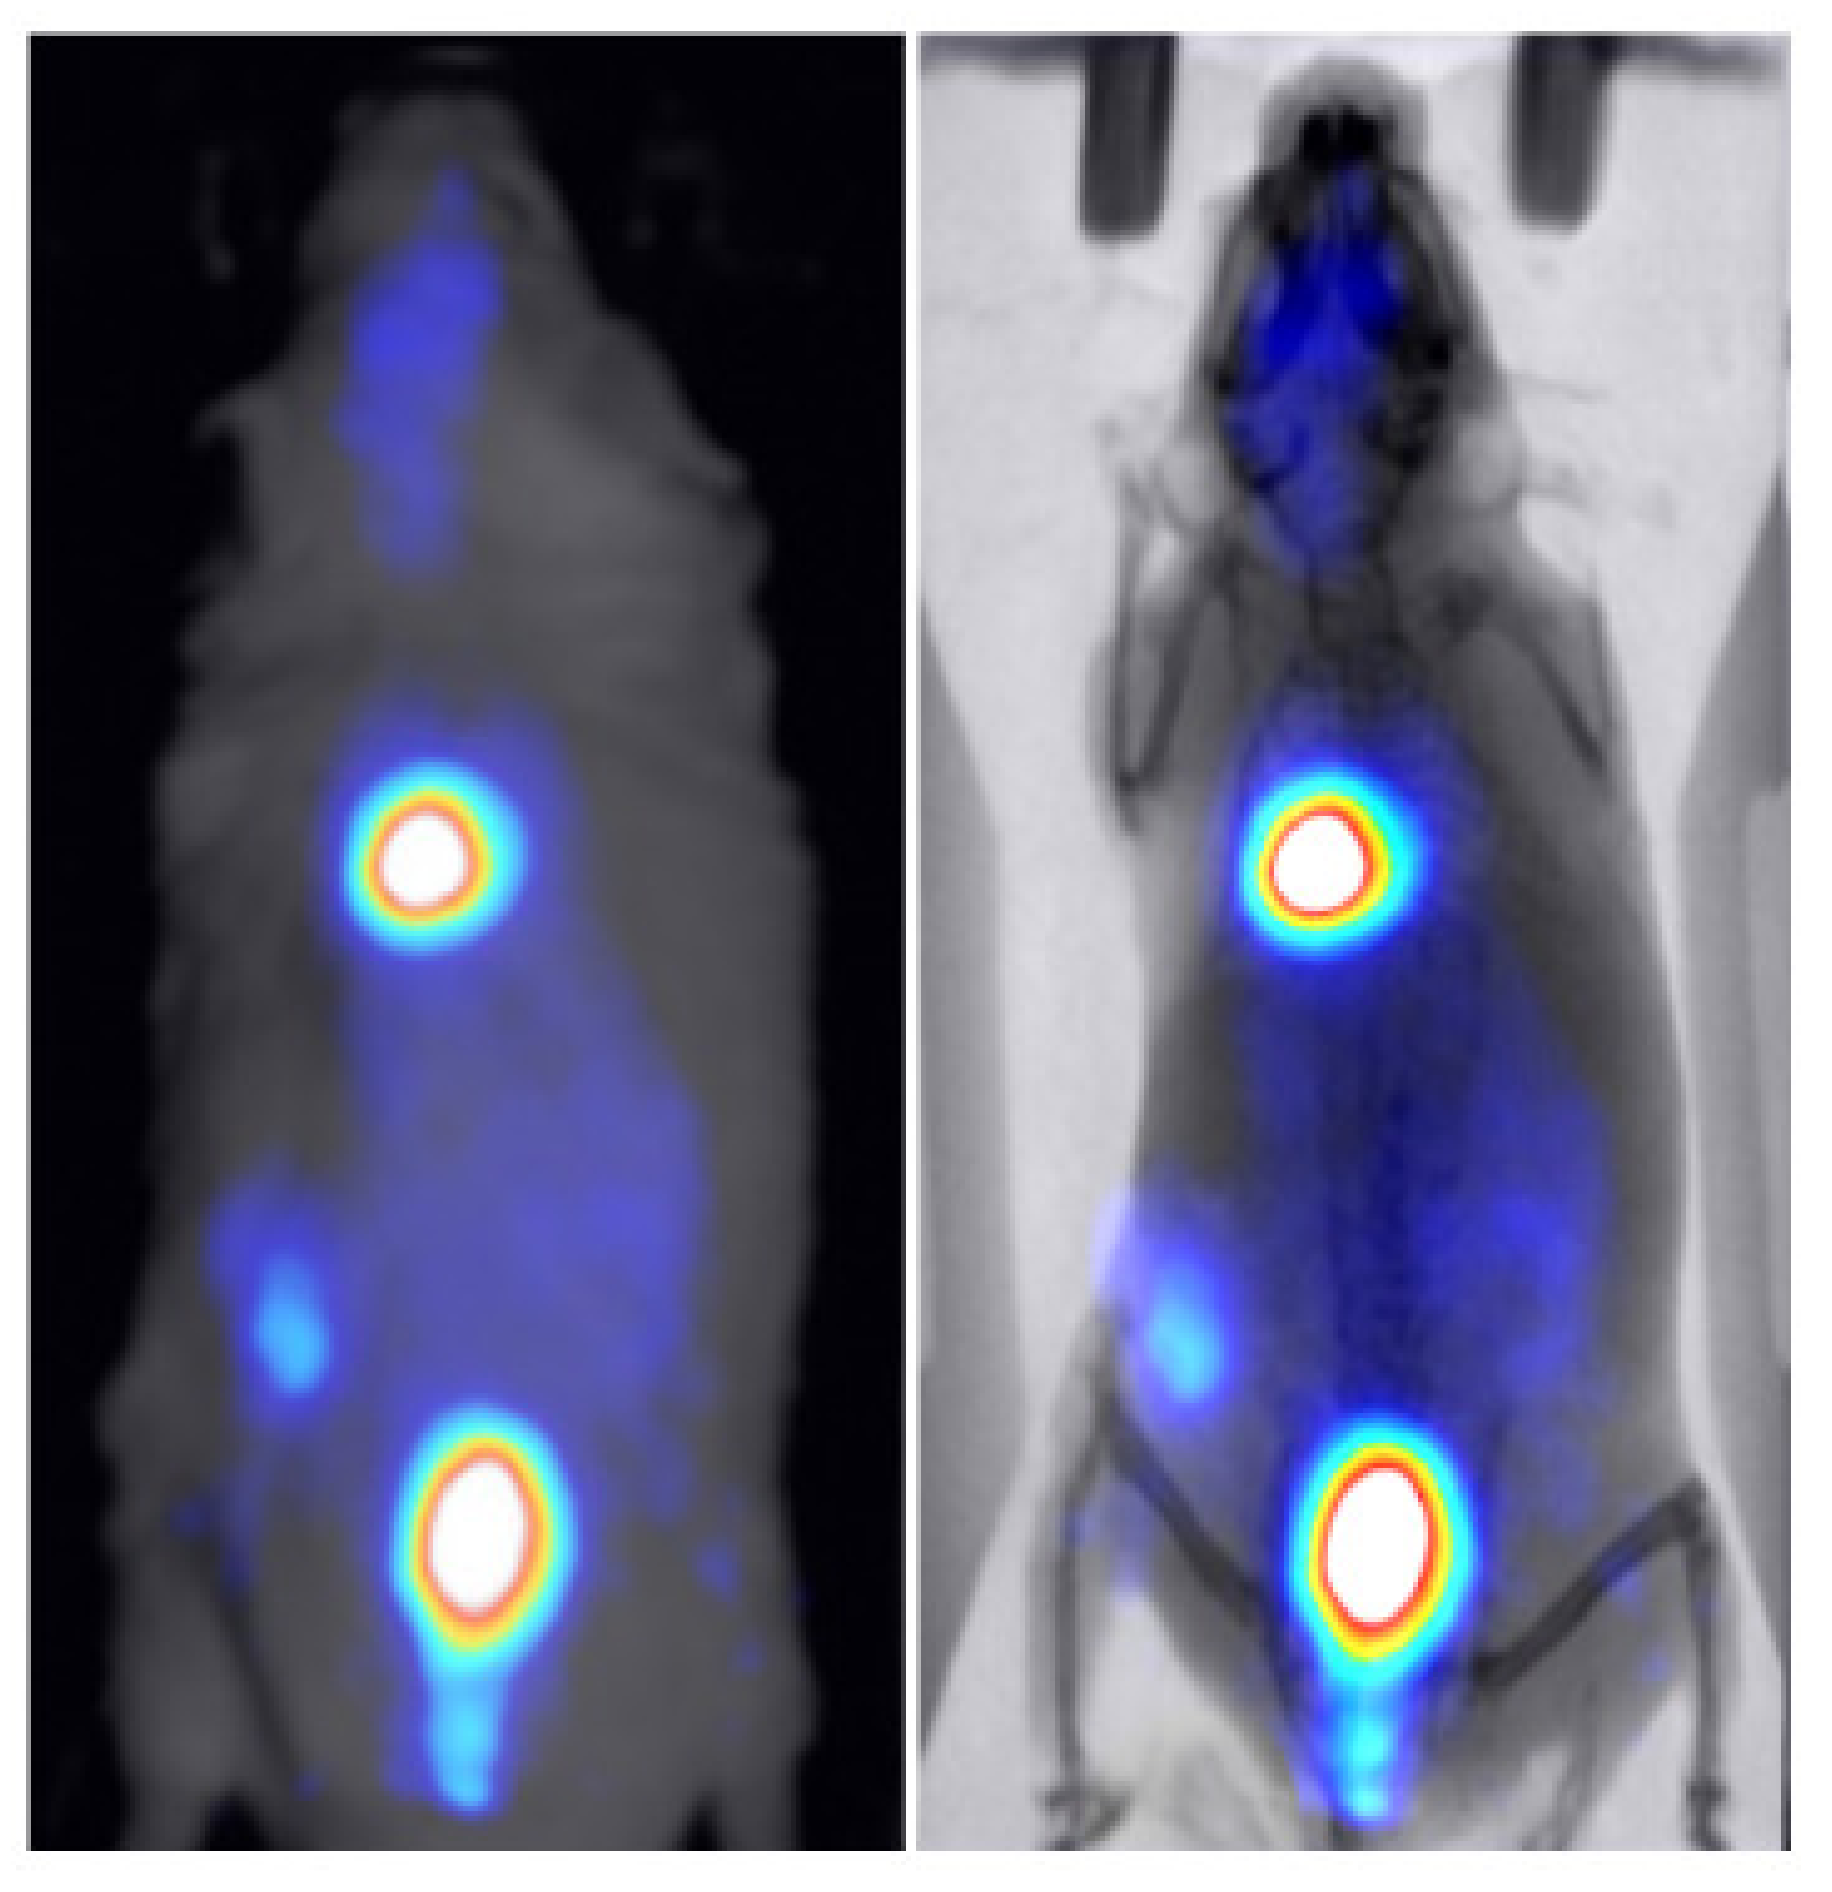

3.2. Animal Mapping during In Vivo Molecular Imaging Experiments